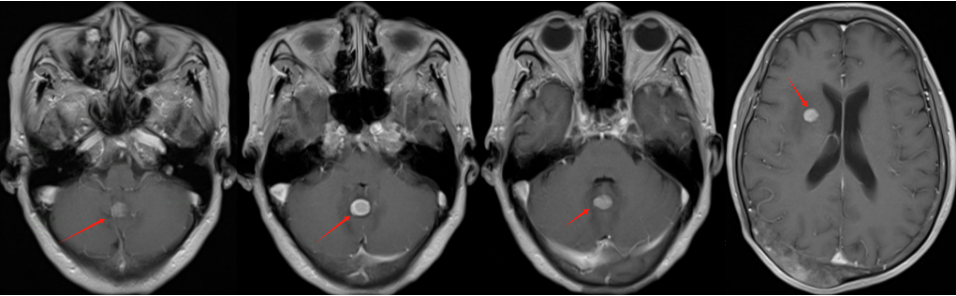

林老先生,67歲,患者2024年8月因咳嗽、咳痰,并發(fā)現(xiàn)頸部包塊入院。入院后經(jīng)CT檢查發(fā)現(xiàn),肺內(nèi)及頸部可見多發(fā)腫瘤病灶(見圖)。于2024年8月21日行超聲引導(dǎo)下頸部淋巴結(jié)穿刺活檢術(shù)。術(shù)后病理提示:右頸轉(zhuǎn)移性肺腺癌。頭部磁共振檢查顯示,顱內(nèi)多發(fā)腦轉(zhuǎn)移瘤病灶(見圖)。診斷為肺腺癌,腦、頸部淋巴結(jié)、肺內(nèi)多發(fā)轉(zhuǎn)移IVB期。進(jìn)一步對(duì)患者腫瘤組織進(jìn)行腫瘤組織基因檢測(cè)和免疫檢查點(diǎn)分子——細(xì)胞程序性死亡配體1(PDL1)檢測(cè)。

圖注:磁共振檢查,顱內(nèi)多發(fā)腦轉(zhuǎn)移瘤病灶。

患者基因檢測(cè)結(jié)果為陰性,沒有找到具有靶向治療藥物的突變基因。此外,患者年齡較大,體質(zhì)非常瘦弱,全身多發(fā)轉(zhuǎn)移病灶,為治療帶來了巨大的挑戰(zhàn)。然而,患者PDL1檢測(cè)顯示,PDL1高表達(dá)(PD-L1患者TPS98% CPS100%),提示免疫治療有效率較高。潘振宇教授團(tuán)隊(duì)為患者制定了個(gè)體化精準(zhǔn)腫瘤治療方案,患者于2024年9月21日開始接受頭部放療。采用最新一代智慧化精準(zhǔn)放療系統(tǒng)——Halcyon“速銳刀”,成功控制患者全部顱內(nèi)病灶。治療過程順利,沒有副反應(yīng)發(fā)生。隨后,給予患者每3周1次免疫治療。經(jīng)過3次免疫治療后復(fù)查,患者肺內(nèi)病灶顯著縮退,癥狀明顯恢復(fù),沒有明顯副反應(yīng)發(fā)生。目前狀態(tài)恢復(fù)良好,生活完全自理。

圖注:治療后復(fù)查磁共振顯示,T1增強(qiáng)掃描可見顱內(nèi)強(qiáng)化轉(zhuǎn)移病灶較前明顯縮退,部分消失。